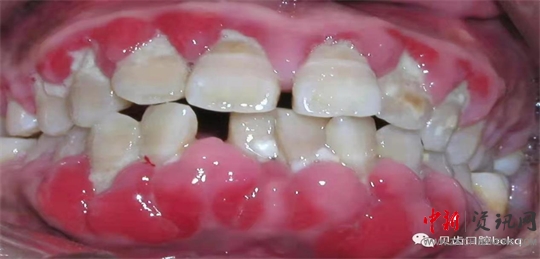

牙周細(xì)菌導(dǎo)致的炎癥,只要造成骨頭的流失,我們就叫它牙周炎。牙周炎在中國(guó)老百姓當(dāng)中是比較普遍,大約有80%-90%的發(fā)病率。以往人們對(duì)于牙周的重視程度不夠,結(jié)果導(dǎo)致后期牙根暴露,牙齒松動(dòng),甚至到最后不得不拔掉松動(dòng)的患牙。

下面這兩張x光片是比較典型的牙周炎的影像資料。該患者的全口所有牙齒都出現(xiàn)了不同程度的松動(dòng);颊攥F(xiàn)在感覺(jué)無(wú)法用牙齒咀嚼。坦白地講,牙周炎發(fā)展到這種程度,很多時(shí)候醫(yī)生也束手無(wú)策了。為了保留更多的牙槽骨,醫(yī)生回不得不拔掉哪些嚴(yán)重松動(dòng)的患牙。